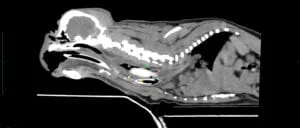

There doesn't seem to be anything stuck. So why is Gnasher still not feeling well? Gnasher was referred to London Veterinary Specialists to see our ECC consultant Dr Alex Hatch. He decided we should take a closed look by performing a computed tomographic or CT study. A CT is like a 3-D x-ray and provides much more information than a standard x-ray. So is there anything stuck in Gnashers oesophagus that we just couldn't see in the x-ray (Figures 2 and 3. A video of the CT study is available on request).

Figure 2: A single CT slice showing a blockage in Gnashers oesophagus (arrows).

Figure 3: A single CT slice showing a blockage in Gnasher's oesophagus (arrows).